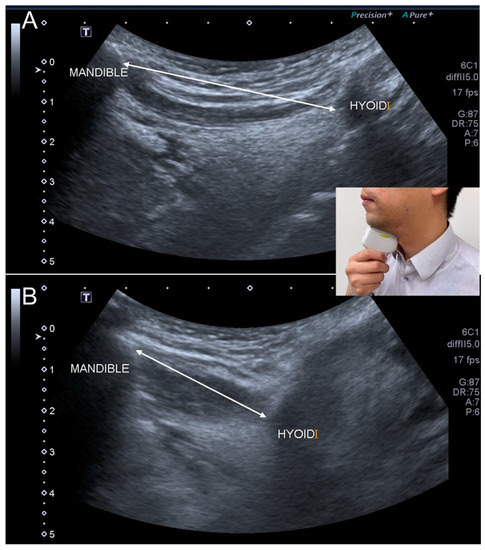

- Ogawa, N.; Mori, T.; Fujishima, I.; Wakabayashi, H.; Itoda, M.; Kunieda, K.; Shigematsu, T.; Nishioka, S.; Tohara, H.; Yamada, M.; et al. Ultrasonography to Measure Swallowing Muscle Mass and Quality in Older Patients With Sarcopenic Dysphagia. J. Am. Med. Dir. Assoc. 2018, 19, 516–522. [Google Scholar] [CrossRef]

- Mori, T.; Wakabayashi, H.; Ogawa, N.; Fujishima, I.; Oshima, F.; Itoda, M.; Kunieda, K.; Shigematsu, T.; Nishioka, S.; Tohara, H.; et al. The Mass of Geniohyoid Muscle Is Associated with Maximum Tongue Pressure and Tongue Area in Patients with Sarcopenic Dysphagia. J. Nutr. Health Aging 2021, 25, 356–360. [Google Scholar] [CrossRef] [PubMed]

- Ogawa, N.; Wakabayashi, H.; Mori, T.; Fujishima, I.; Oshima, F.; Itoda, M.; Kunieda, K.; Shigematsu, T.; Nishioka, S.; Tohara, H.; et al. Digastric muscle mass and intensity in older patients with sarcopenic dysphagia by ultrasonography. Geriatr. Gerontol. Int. 2021, 21, 14–19. [Google Scholar] [CrossRef] [PubMed]

- Chen, Y.C.; Chen, P.Y.; Wang, Y.C.; Wang, T.G.; Han, D.S. Decreased swallowing function in the sarcopenic elderly without clinical dysphagia: A cross-sectional study. BMC Geriatr. 2020, 20, 419. [Google Scholar] [CrossRef]